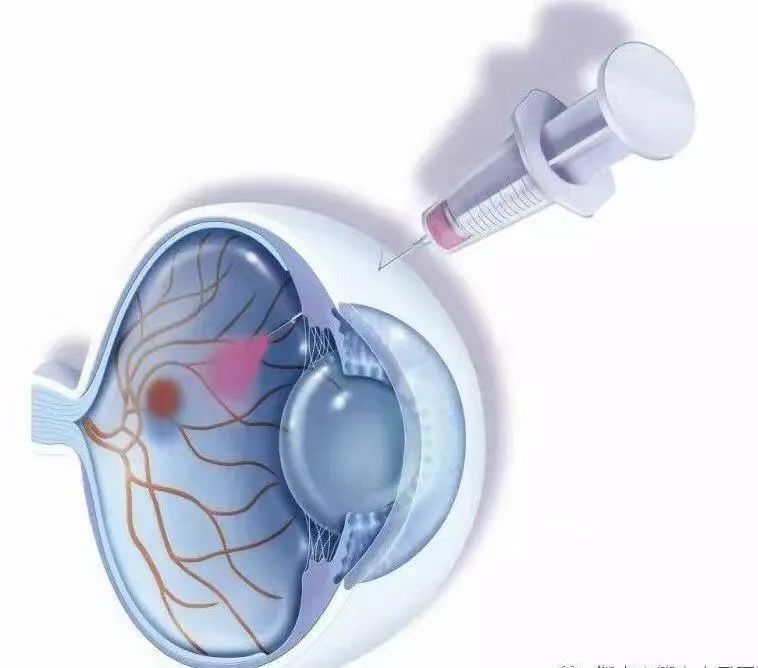

药物治疗:通过眼内打针即玻璃体腔局部注射抗VEGF药物、糖皮质激素治疗糖性黄斑水肿。局部抗VEGF药物需在专业眼科医生指导下遵医嘱按需注射。

眼内打针是什么意思?

眼内打针,多指向眼内玻璃体腔内注射抗血管内皮生长因子(VEGF)药物。VEGF是参与糖尿病黄斑水肿病理生理过程的一个重要因子,缺氧、高血糖等病理条件可能导致VEGF上调,进而引起渗漏、血管增生等病理过程。已有大量证据显示抗VEGF治疗在糖尿病黄斑水肿治疗中的疗效。目前,临床常用抗VEGF制剂包括雷珠单抗、阿柏西普、康柏西普等。玻璃体腔内注射抗VEGF适用于威胁视力的糖尿病性黄斑水肿。